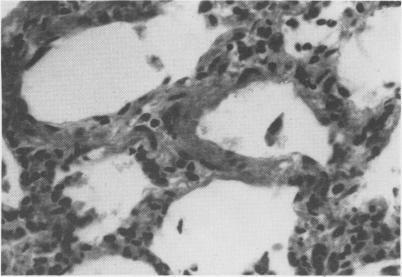

[Progressive interstitial pneumonia of sheep].

Can Vet J. 1974 Oct;15(10):293-7.